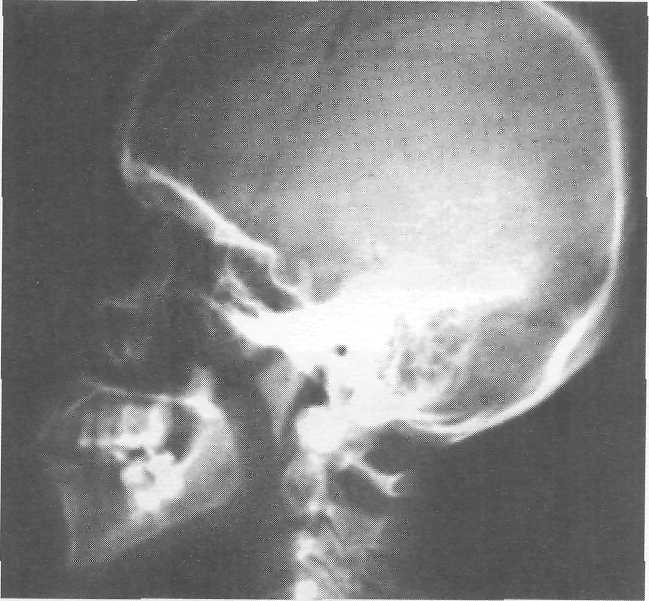

· Citeste mai mult « 1680 cuvinte, 4 pag. » RADIOLOGIE MD IV

Prezentarea problematicii generale a tipului de

radiografii care se adreseaza preferential teritoriului

dento-parodontal

NCiteste mai mult « 2121 cuvinte, 5 pag. » PRINCIPII DE GENETICA

RADIOLOGIE

MEDICO-DENTARA CURS MD

CURSUL

NR II

RADIODIAGNOSTICUL

STOMATOLOGIC

§Este o componenta importanta a radiologiei medicale .

§Radiologia medicala

§-este stiinta utilizarii in medicina a radiatiilor

profound penetranteCiteste mai mult « 900 cuvinte, 2 pag. » Filarii